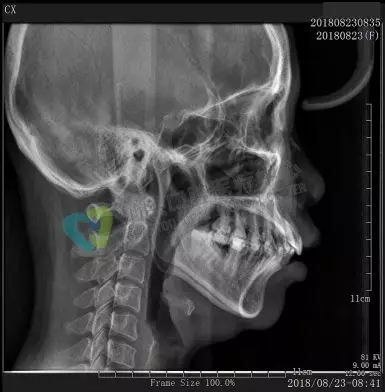

口腔全景牙片,是通過(guò)一次拍攝將全口牙齒和頜骨的影像清晰的顯示在一張X光片上,可以清晰、完整的顯示上頜骨、下頜骨全貌,上下頜牙列情況,牙槽骨情況,能夠清晰顯示上頜竇腔、竇壁、竇底情況以及顳頜關(guān)節(jié)情況,并對(duì)頜骨周?chē)膊〉脑\斷提供準(zhǔn)確有效的幫助。